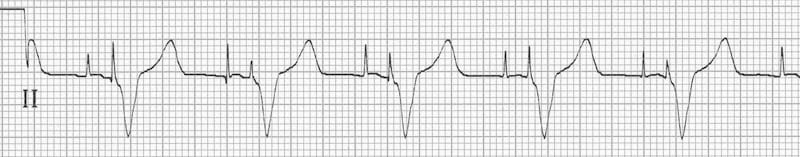

Can you work out what is going on in this ECG?

Answer and interpretation

- There is an irregularly irregular rhythm with multiple atrial and ventricular pacing spikes.

- The majority of the QRS complexes are broad (120ms) and preceded by ventricular pacing spikes.

- The LBBB morphology is consistent with a ventricular pacing electrode located in the right ventricle.

The varying relationship between the atrial and ventricular pacing spikes is best understood by examining the lead II rhythm strip (below):

- Beat 1 is narrow — this appears to be a native ventricular complex triggered by an atrial pacing spike. This indicates that AV conduction is intact to some degree (i.e. 3rd degree AV block cannot be present).

- Beat 9 is broad with a completely different morphology and axis to the rest of the strip — this is a ventricular ectopic beat.

- Beats 3, 6, 8, 10 and 12 are preceded by both atrial and ventricular pacing spikes — sequential A-V pacing.

- Beats 2, 4, 5, 7 and 11 are preceded by ventricular pacing spikes only. The absence of atrial pacing spikes suggests that the pacemaker is responding to native supraventriclar impulses.

- Given the absence of discernible P waves and the very irregular rhythm, it is likely that the underlying native rhythm is atrial fibrillation.

Conclusion

- Atrial fibrillation with DDD pacing and occasional ventricular ectopics.